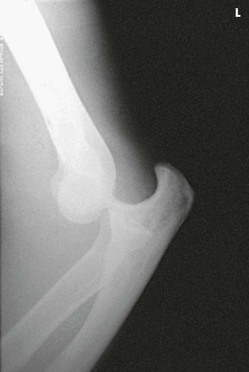

Structures shown

The lateral projection shows the elbow joint, distal arm, and proximal forearm (see Figs. 4-113 and 4-114).